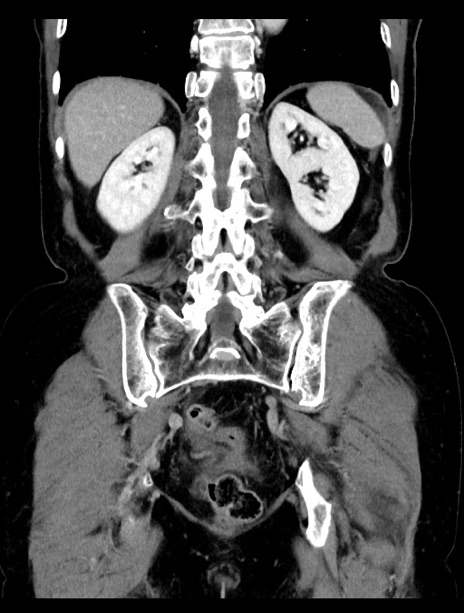

症例23(冠状断像)

【症例】70歳代女性

【主訴】下腹部痛・嘔吐

【現病歴】2日前より腹痛あり。昨日嘔吐あり。症状改善しないため来院。

【既往歴】胃GISTに対して胃部分切除後。

【身体所見】BT 37.1℃、BP 128/77mmHg、腹部:平坦・軟、下腹部に圧痛あり。

【データ】WBC 10200、CRP 0.31